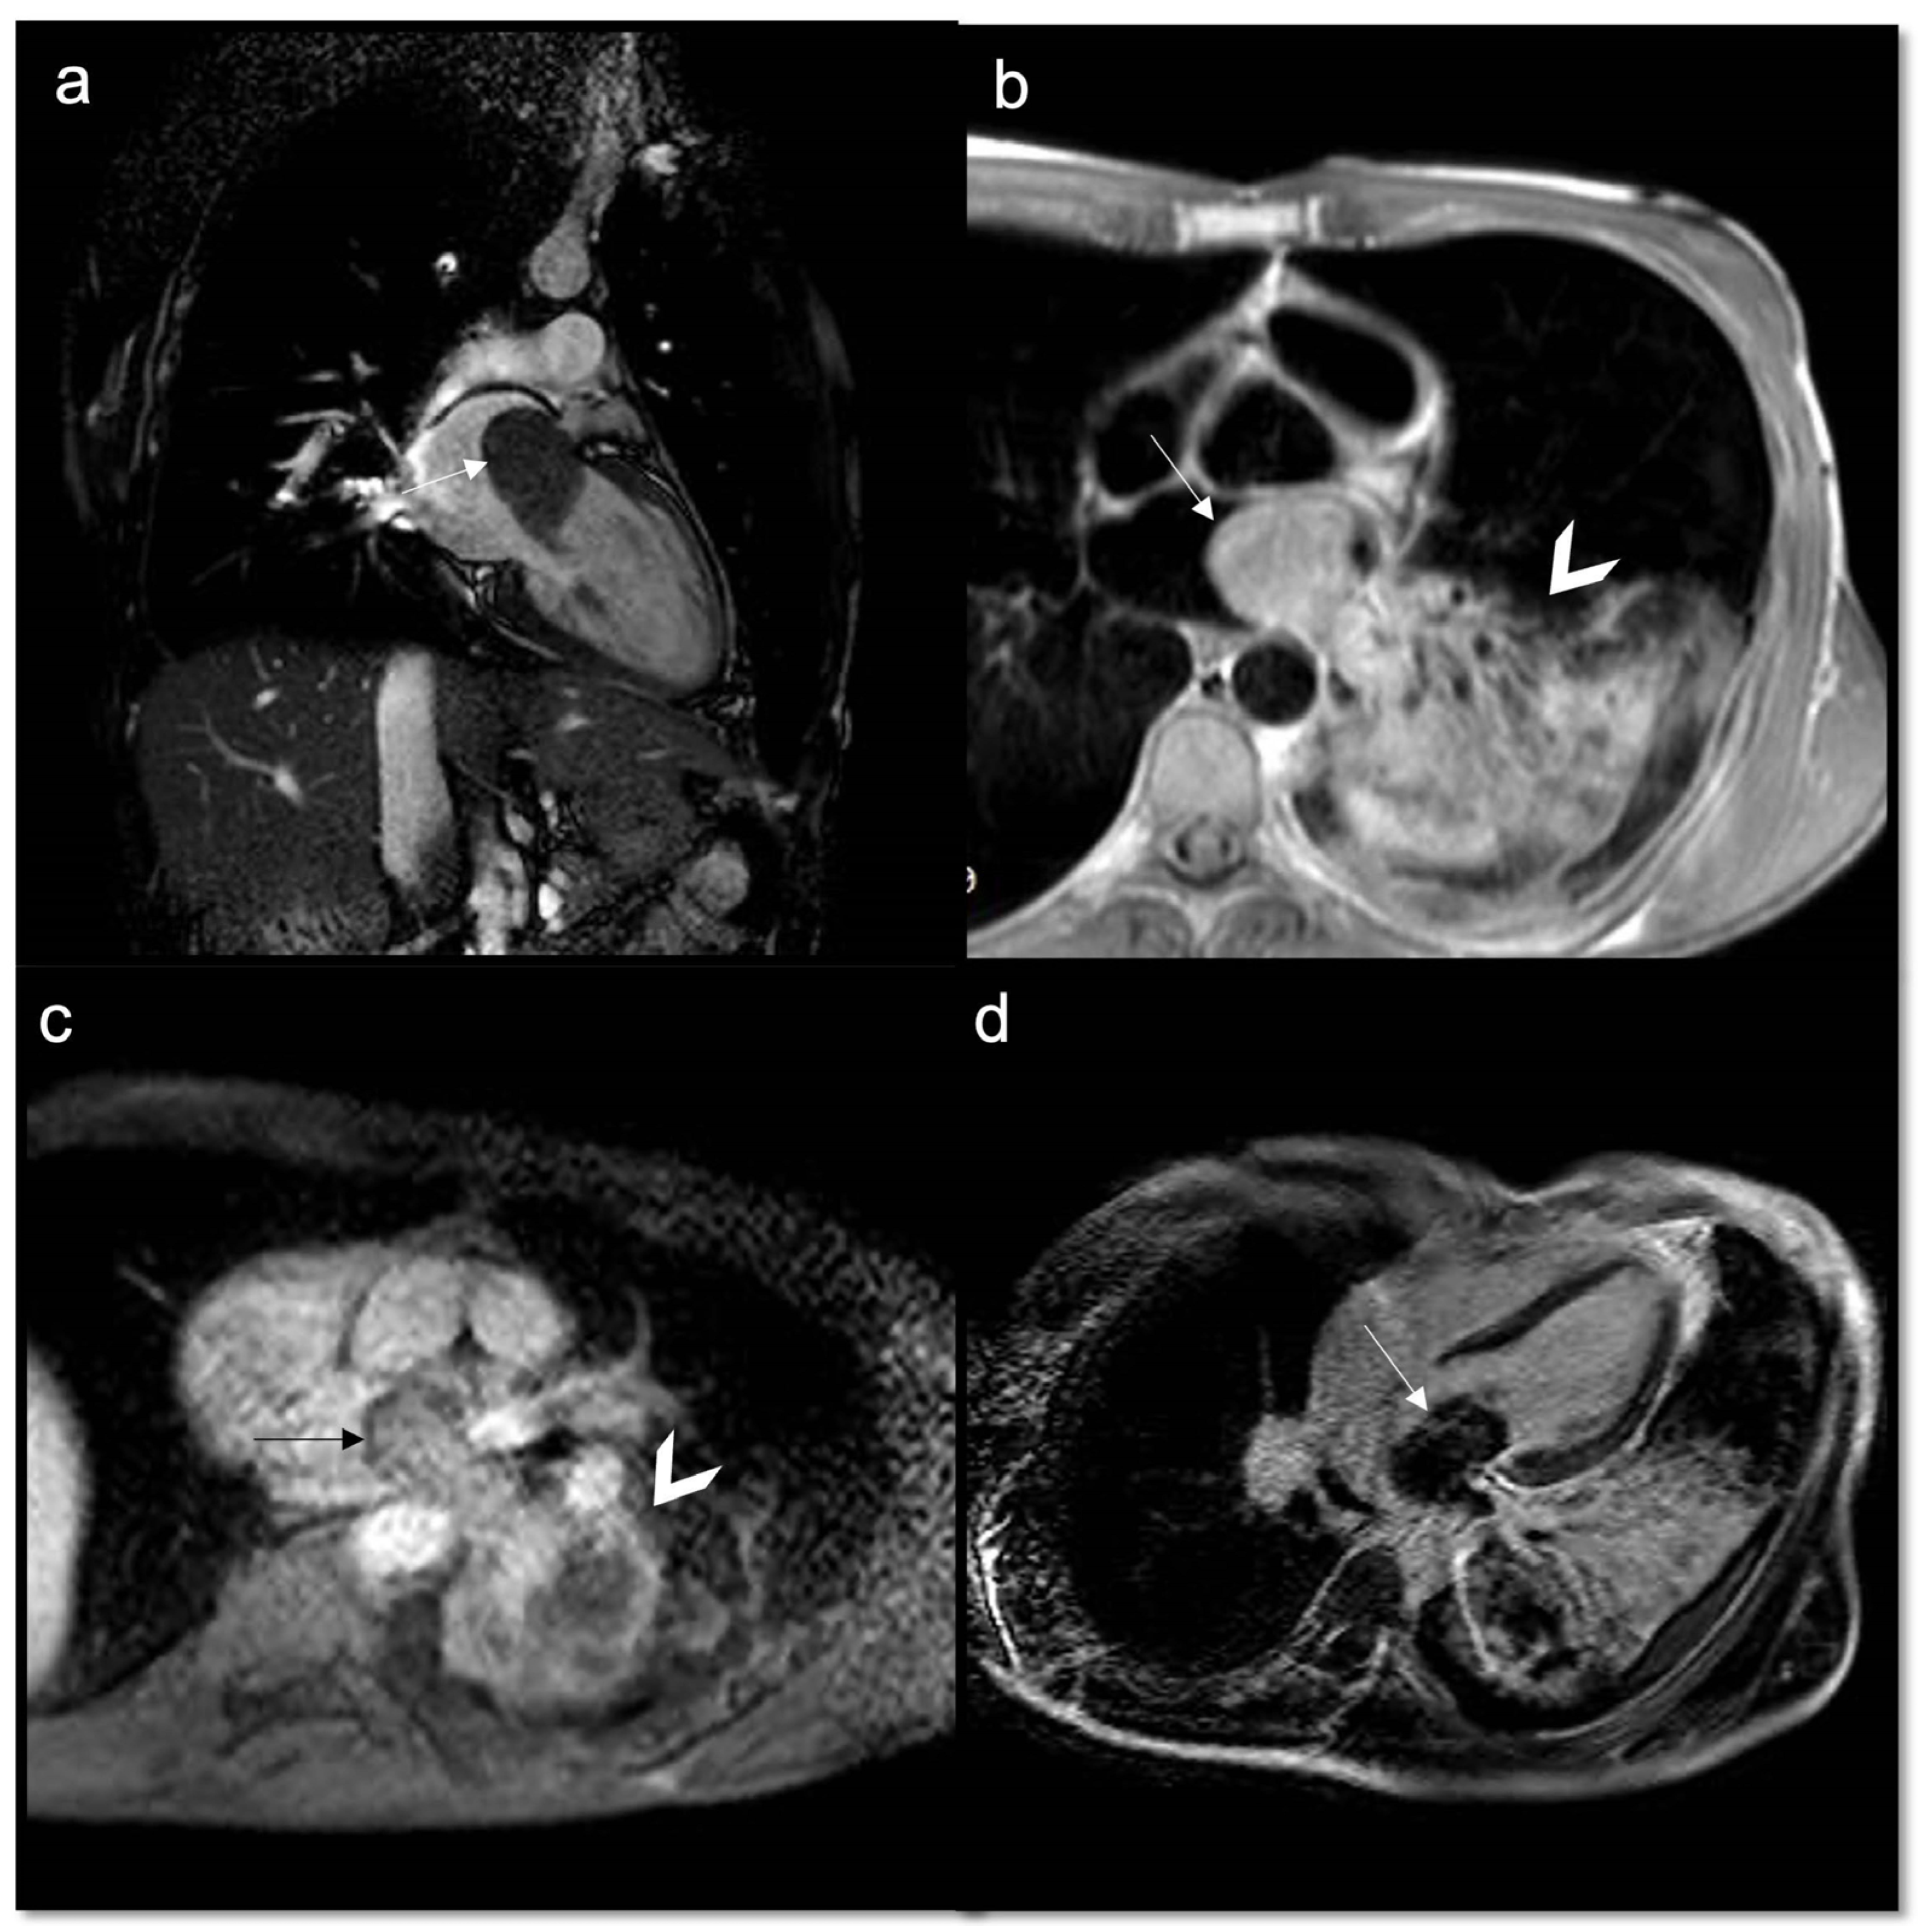

Figure 1.

A 46-year-old woman with retrosternal pain during exertion and non -ST elevation myocardial infarction underwent coronarography. The interventional procedure showed stenosis of the common trunk treated with bifurcation stent implantation. Later, due to the unexplained pericardial effusion, the patient underwent coronary computed tomography angiography (CCTA) which revealed a voluminous pseudoaneurysm (arrow) of the left coronary sinus (a,b). Cardiac surgery was performed to exclude pseudoaneurysm and to perform a by-pass (c). After the cardiac surgery, the patient performed a CCTA that showed the exclusion of the pesudoaneurysm (d). Four months later, when the patient was back for a follow-up, CT angiography showed a mass with peripheral enhancement, central hypodensity due to necrosis, and central neoangiogenesis (e). Finally, the patient underwent CMR that confirmed the presence of inhomogeneous mass invading the surrounding structures (f) and neoplasia was suspected. Lastly, the ultrasound-guided transesophageal biopsy has shown the presence of fused and pleomorphic malignant cells with leiomuscular immunophenotype (actin 1A4 +) and the diagnosis of leiomyosarcoma was made.

Figure 2.

A 78-year-old man arrived at the emergency department with a two-week history of progressively worsening dyspnea, cough, and weight loss. CMR cine sequences show a conspicuous pericardial effusion (a) and an ill-defined infiltrative mass (arrow) at the level of the tricuspid valve, hyperintense on T2w Fat Sat (b). Biopsy confirmed it as a primary cardiac lymphoma, a very rare entity.